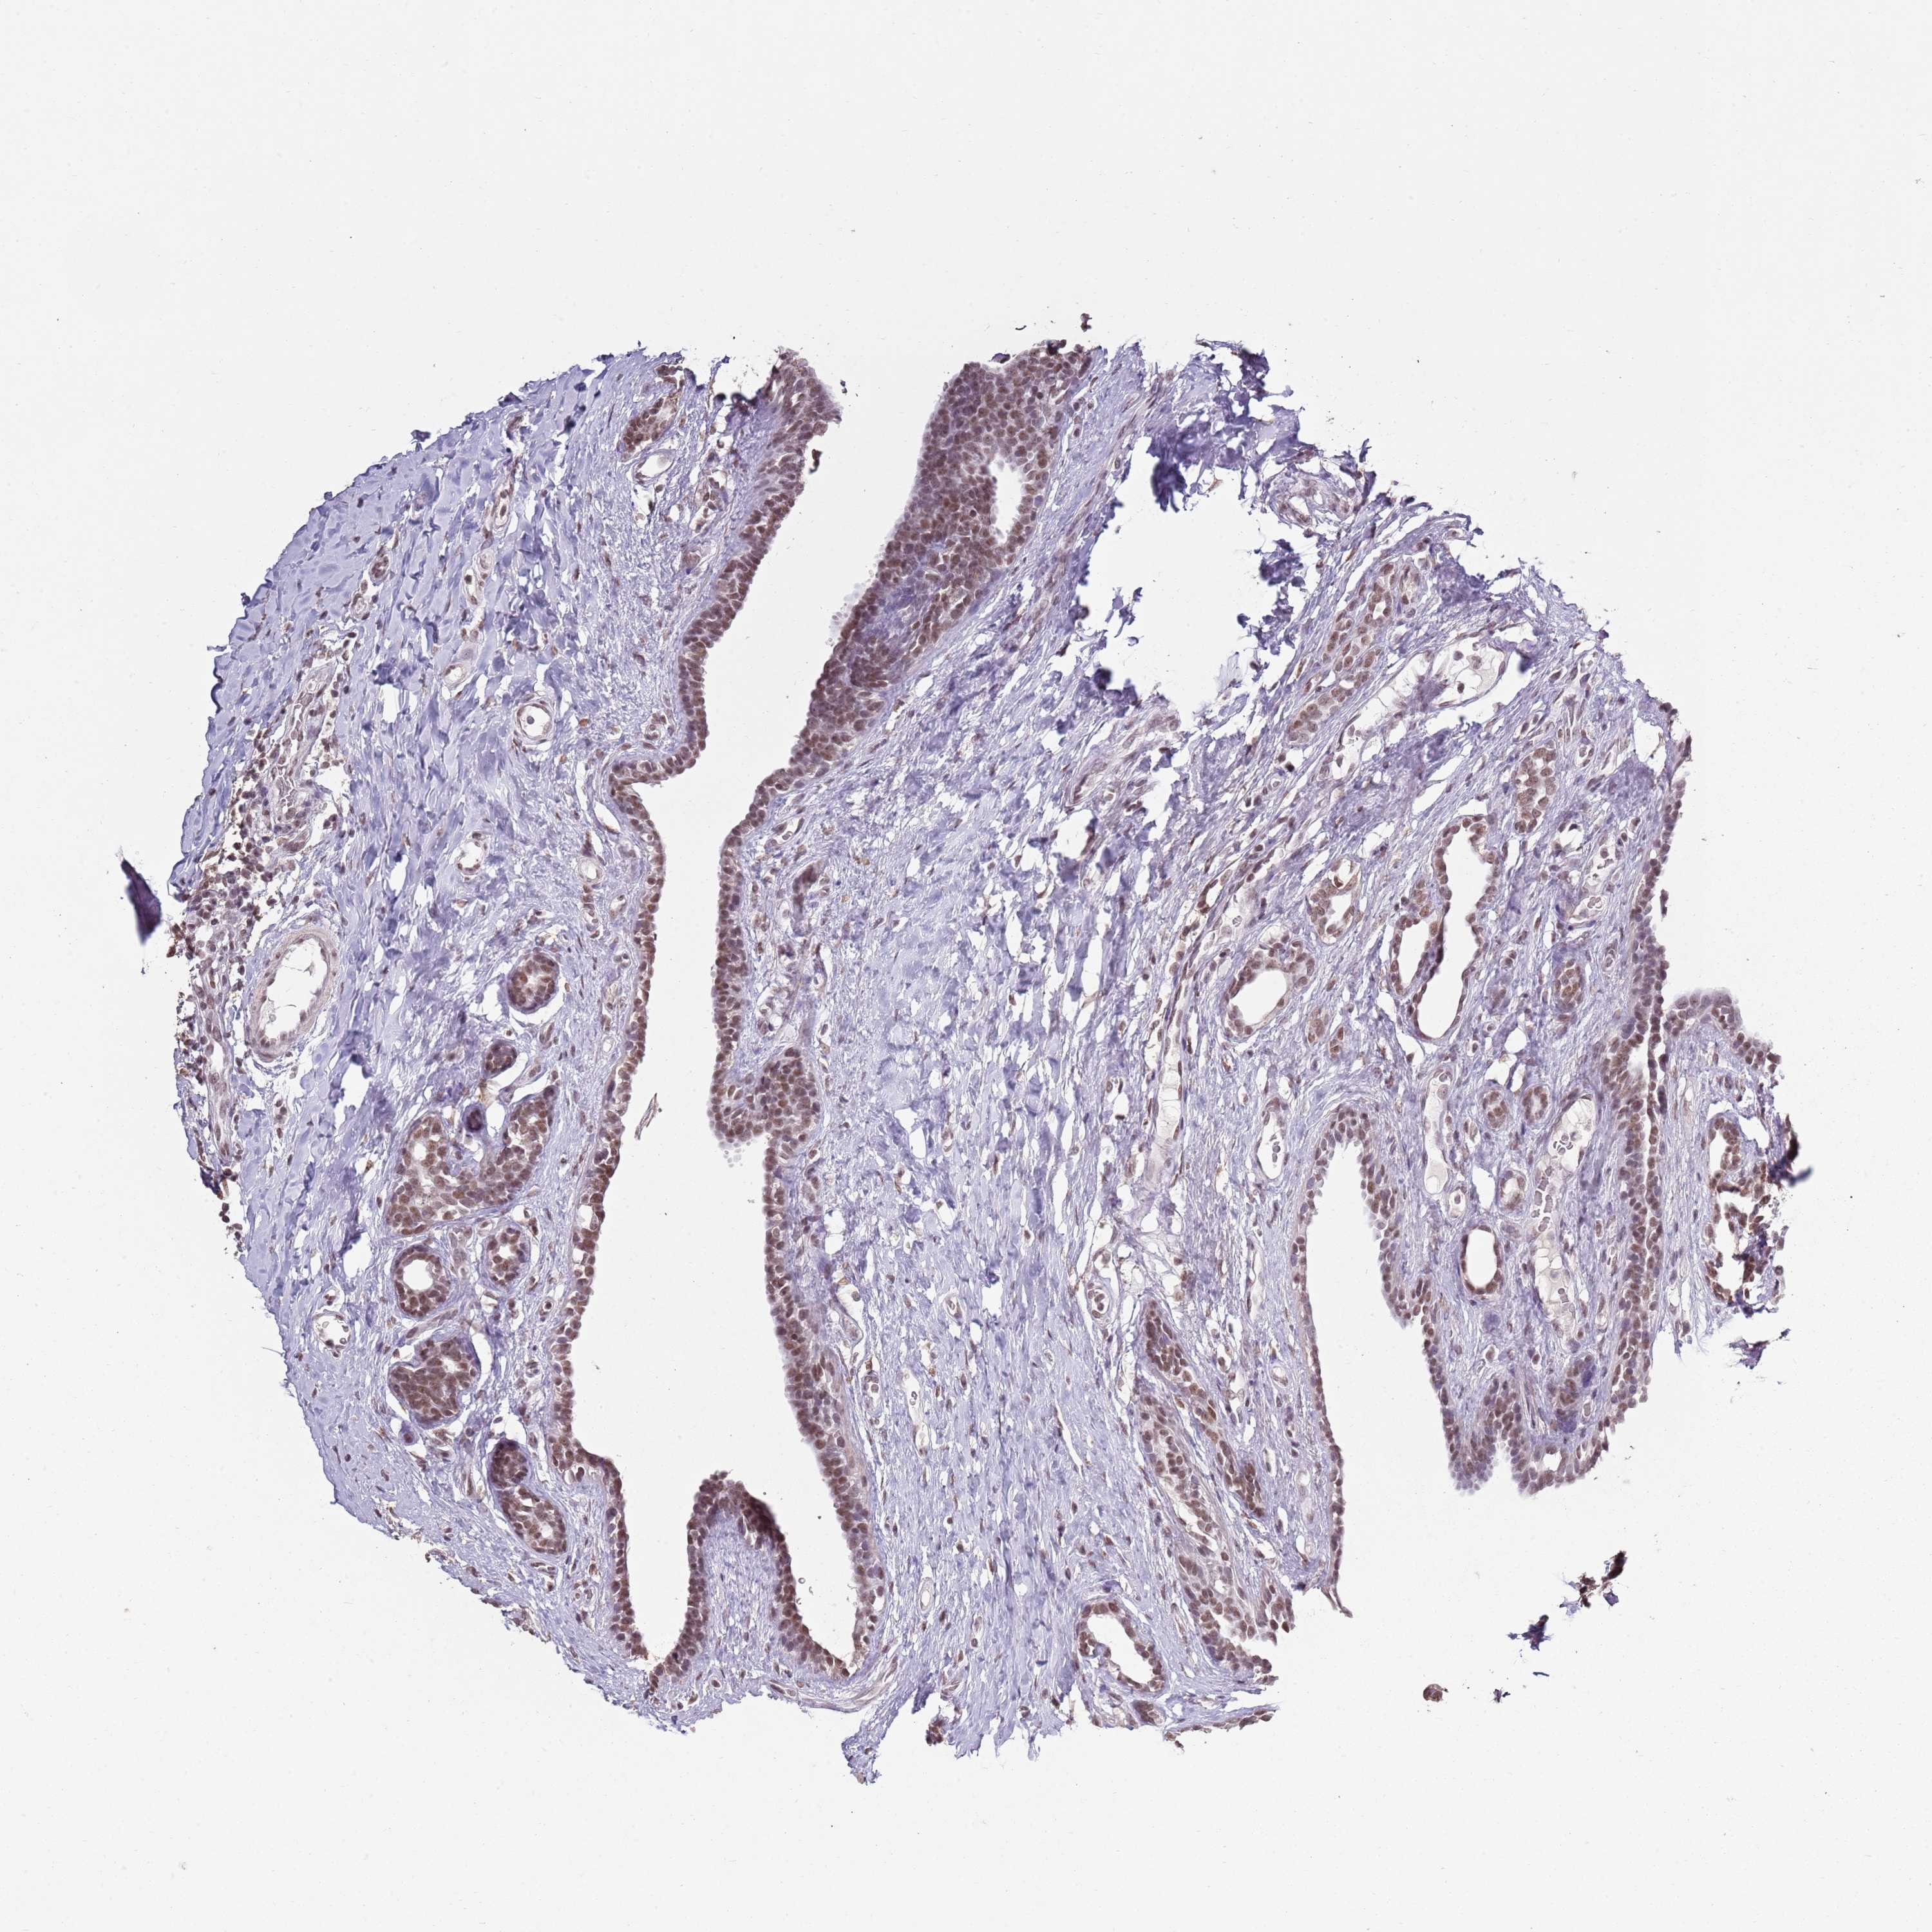

CANCER BREAST CANCER Show tissue menu

BRCA TCGA BRCA VALIDATION PROTEIN EXPRESSION